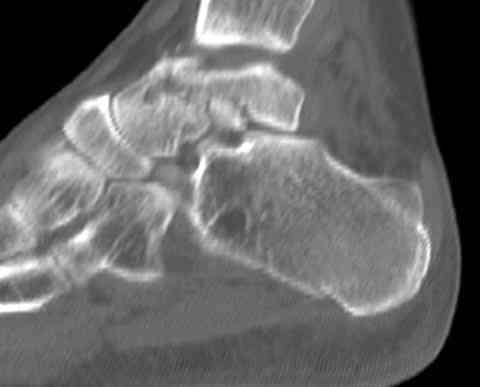

Для оценки состояния нужны дополнительные исследования, например Canale или Broden ренгенограммы и Компьютерная томография.

Случай с множественным оскольчатым переломом тарана оперированный из двойного доступа.